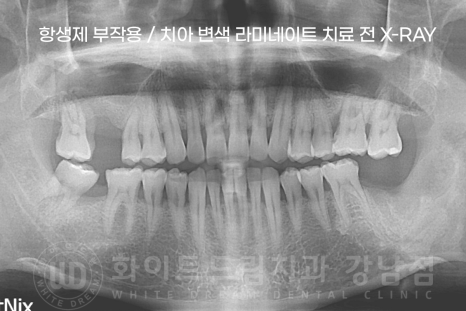

환자분의 치료 전/후 X-RAY를 확인하면 신경치료를 안한 것이 확인되실 겁니다. ^^

치아를 감싸고 있는 에나멜 부분만 안전하게 삭제 후 라미네이트를 부착했습니다.

▲ 테트라사이클린으로 인한 변색은 치아에 줄이 가는 항생제 부작용입니다.

테트라사이클린으로 인한 변색은 영구적이며, 치아미백으로 해결할 수 없습니다.

오히려 치아미백을 하면 변색이 안된 부분이 더 하애지기 때문에 더 차이가 심해 보입니다.

그래서 보통 전치부 보철치료로 개선하는데요.